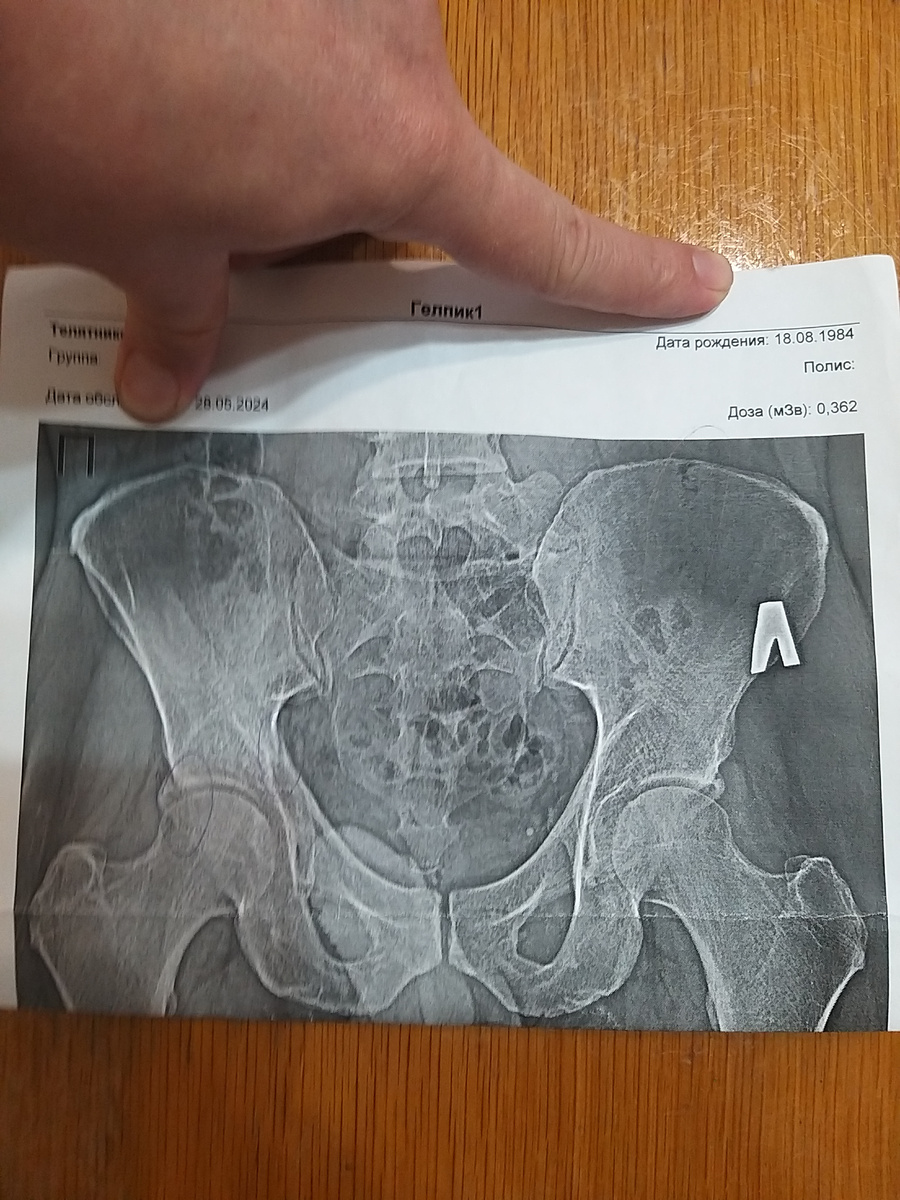

Вот прекрасный рентгеновский снимок моих тазовых костей. На нем хорошо видно, где бвли переломы. Самое интересное, что сломан оказался тазобедренный сустав, о котором я не знал долгое время. Но ничего, теперь все срослось и меня ожидает реабилитация. Я надеюсь, что после нее смогу нормально ходить и вернусь к обычной жизни.